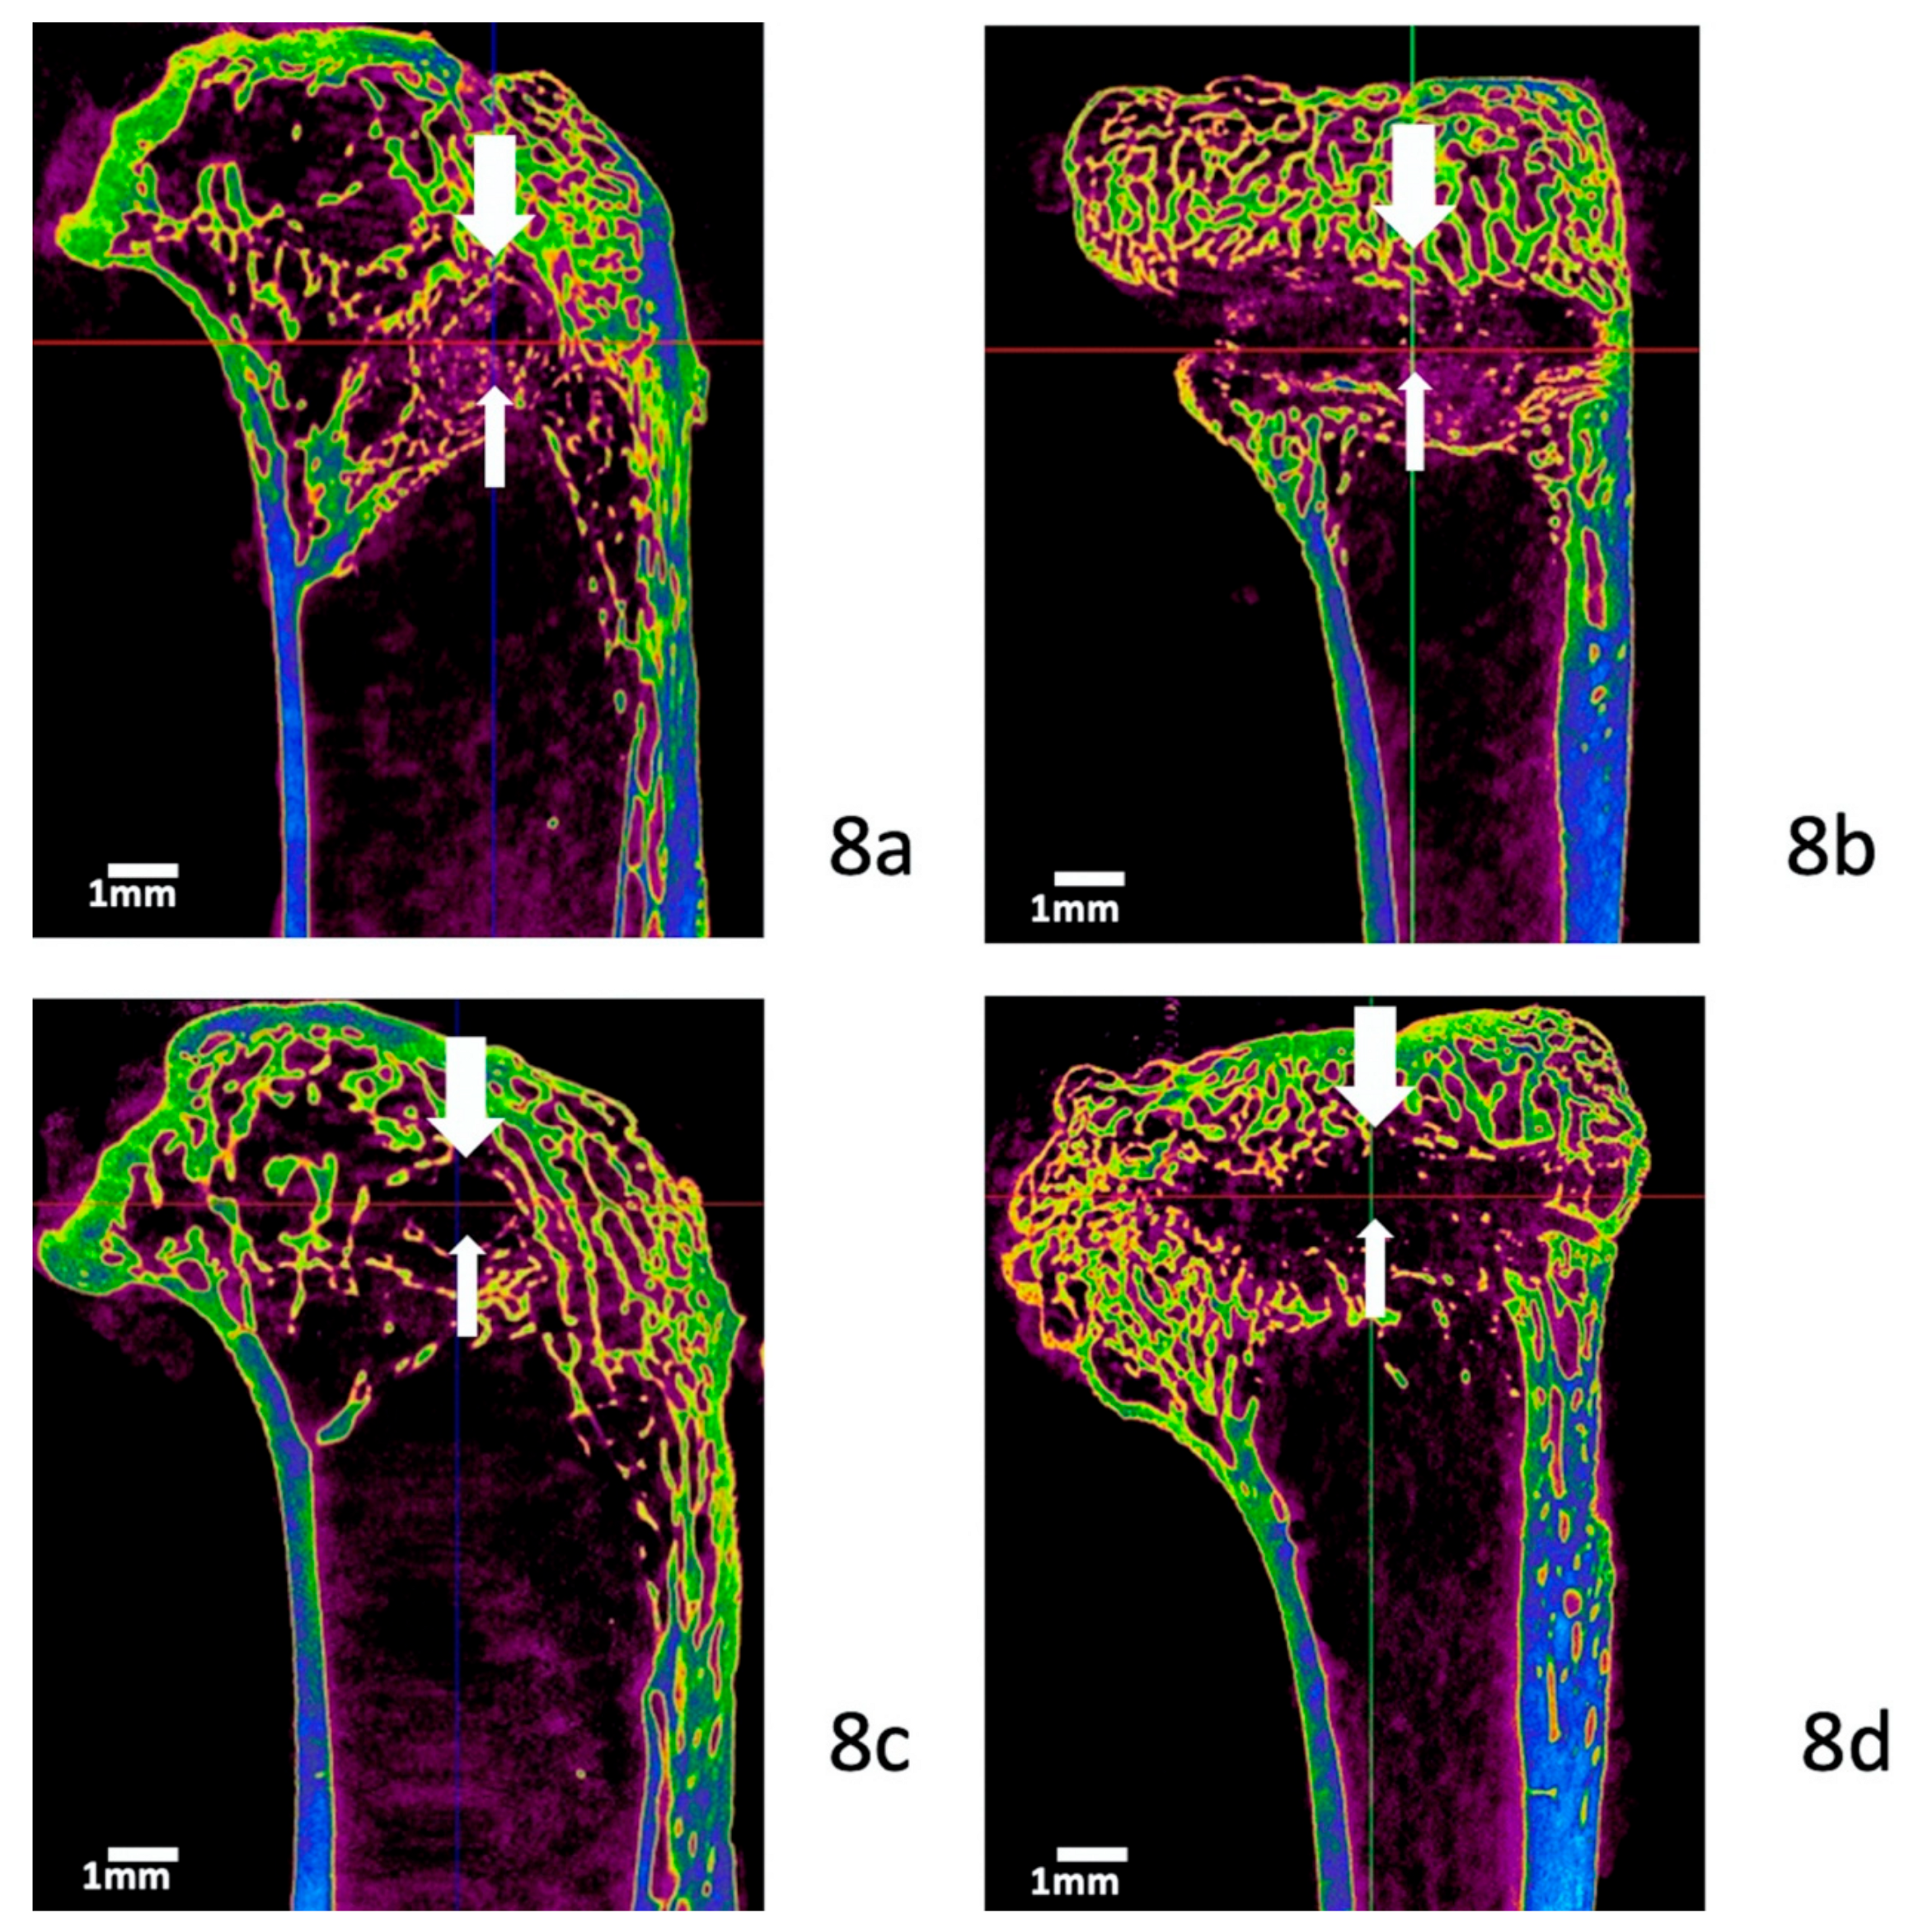

3.5. Micro-Computed Tomography Evaluation